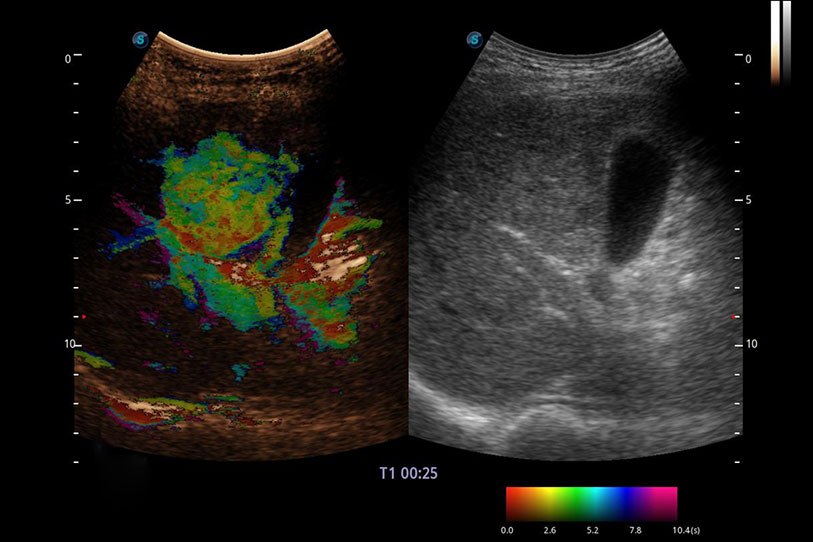

操作簡便,無需高頻度外力作用即可真實(shí)反映組織的形變,快速評估腫瘤良惡性。

采用紅、橙、黃、綠、青、藍(lán)、紫這七種肉眼最為敏感的色彩,直觀地顯示組織內(nèi)血流灌注的時(shí)間先后信息,更精準(zhǔn)捕捉血流灌注走行細(xì)節(jié)。